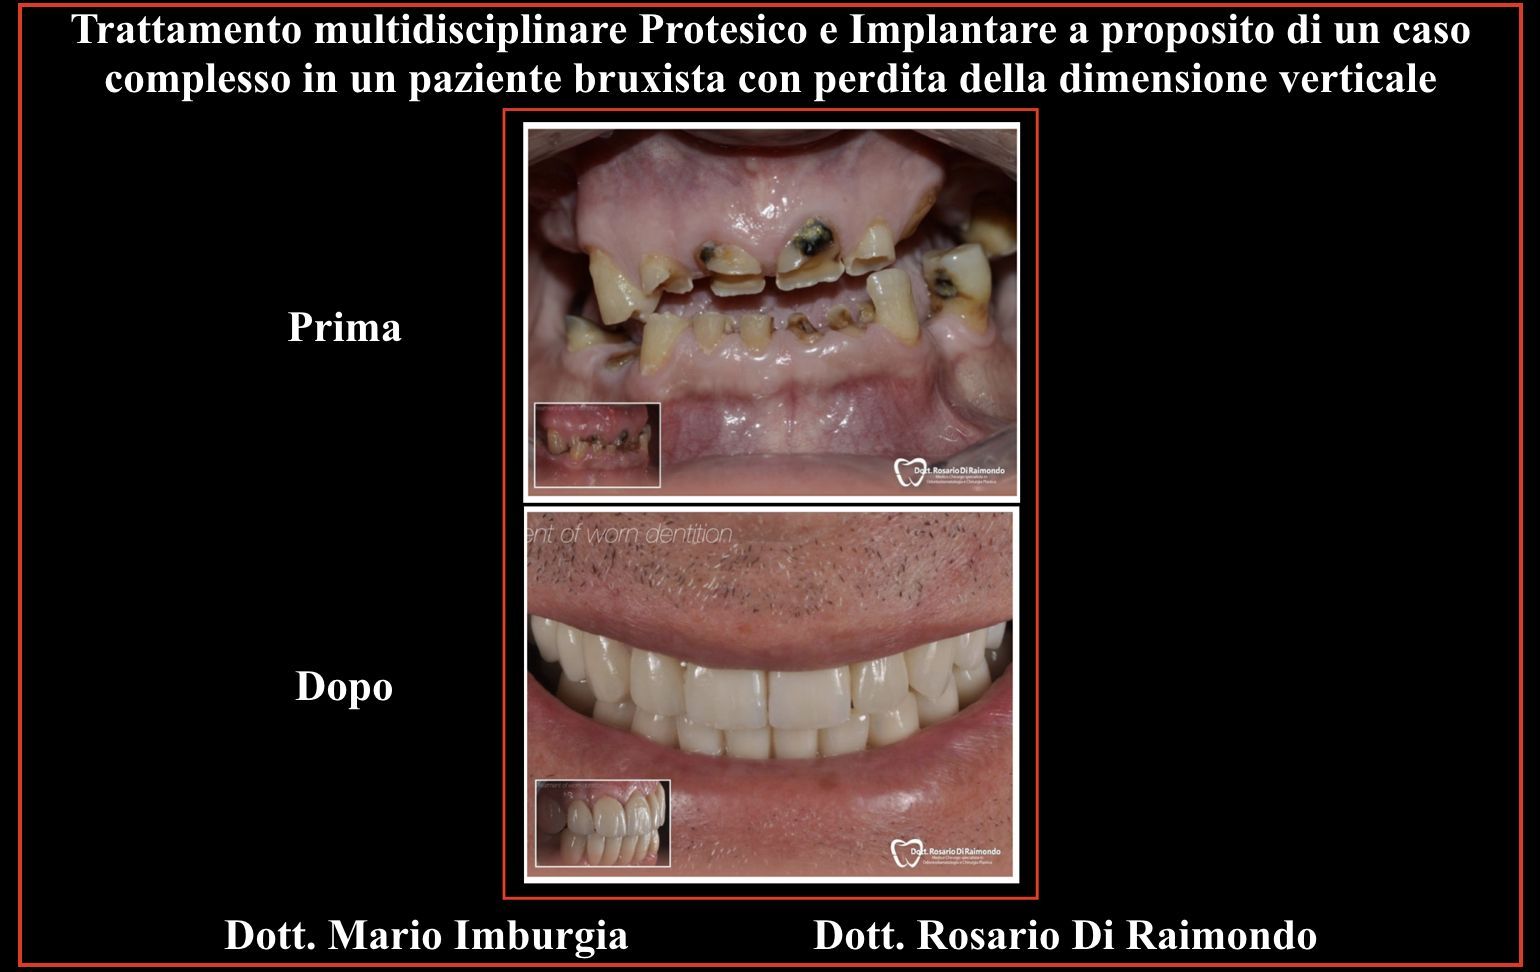

Casi Trattati

Di seguito riportiamo alcune fotografie di casi di Implantologia già trattati.